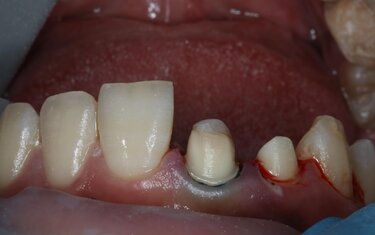

A 43-year-old woman came to my practice for a smile makeover to repair her chipped teeth and close the diastema between teeth #8 and #9 (Figure 8). Upon examination it was clear that the root canals on teeth #12 and #13 were failing and the pre-molar on her left side was compromised. It was decided to place a 4-unit full-contour zirconia bridge on teeth #11-14 and individual crowns in the esthetic zone on teeth #6, 7, 8, 9, and 10 (IPS e.max CAD, Ivoclar Vivadent).

The teeth were prepped (Figure 9), scanned and new restorations designed in CAD software (Chairside CAD, Exocad). We then 3D printed a model and filled the putty wash matrix (Figure 10) with a self-cure composite material (Luxatemp Ultra, DMG) to create temporaries for the patient to wear for a week to get feedback on fit, function and color (Figure 11).

Figure 9: The patient’s teeth were prepped for a 4-unit zirconia bridge on teeth #11-#14 and single full-contour crowns on teeth #6-#10. The preps were scanned and the bridge and individual crowns designed in CAD software.